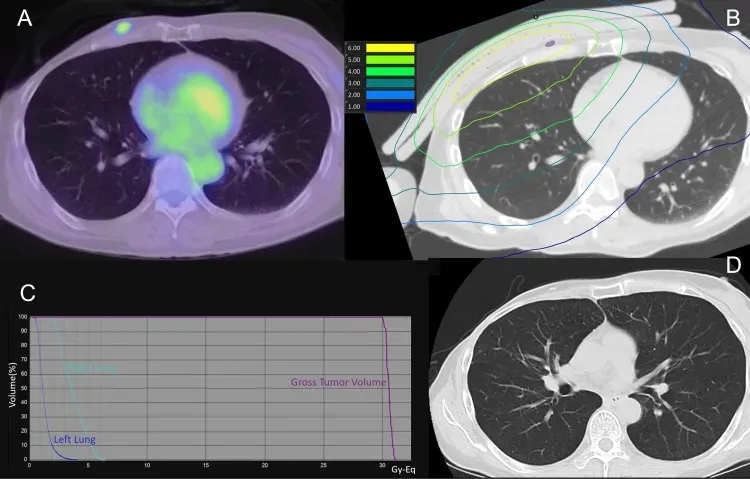

结果显示:在BNCT治疗后1天、7天、30天、60天、90天的CT扫描中,均未发现放射性肺炎迹象。下图3为该患者的肺部剂量分布及治疗后90天的CT扫描影像。

好消息是,日本近期已启动硼中子俘获疗法的临床研究,入组人群仅限不可切除的局部晚期或局部复发的头颈癌、乳腺癌成年患者等。感兴趣的癌友可将治疗经历、近期影像及病理学检查结果,提交至医学部,进行初步评估或了解详细入排标准。